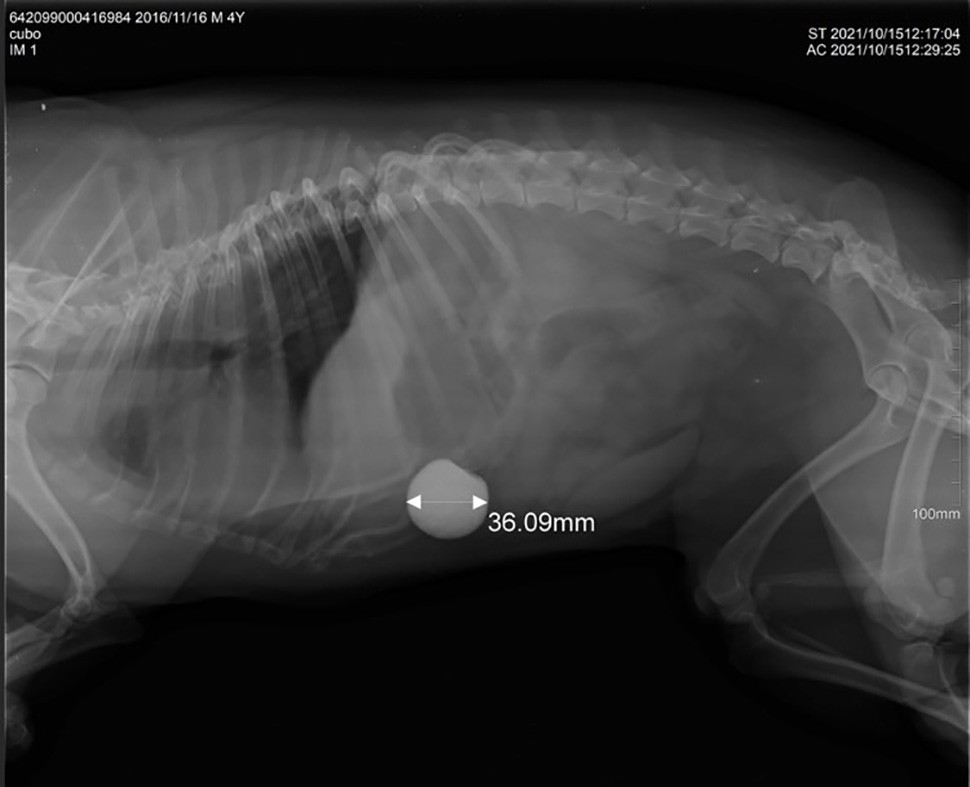

Bélelzáródás Dr. Pálosi Csaba röntgenfelvétele

– Az egészben lenyelt dió, ha a gyomorból a vékonybél felé halad tovább, általában elakad, melynek teljes bélelzáródás lesz a következménye. A kutya bágyadt lesz, nem eszik, nem iszik, egyre gyakrabban hányik, sokszor még a vizet is, ezért óránként válik súlyosabbá az állapota. Erős hasi fájdalom is kíséri, emiatt felhúzott hassal járkál az állat. Kezeletlen esetekben pár napon belül hashártyagyulladás alakulhat ki, kilyukadhat a bélfal.

A földre hullott barack és a szilva húsa nem ártalmas kedvenceinknek, a magvaik ciántartalma is csak nagy mennyiségben okozhat mérgezést. Nagyobb gond azonban, hogy az udvaron, kertben élő kutyák előszeretettel dézsmálják a lehullott gyümölcsöket, meggyet, cseresznyét, és azokat a magokkal együtt nyelik le. A gyomorból vékonybélbe kerülő magok azonban felhalmozódva bélelzáródást okozhatnak, érdes felszínük felsértheti a bélfalat, ami komoly orvosi beavatkozást tesz szükségessé. Egy későn észlelt bélelzáródás sajnos rövid időn belül a kutya halálát okozhatja.